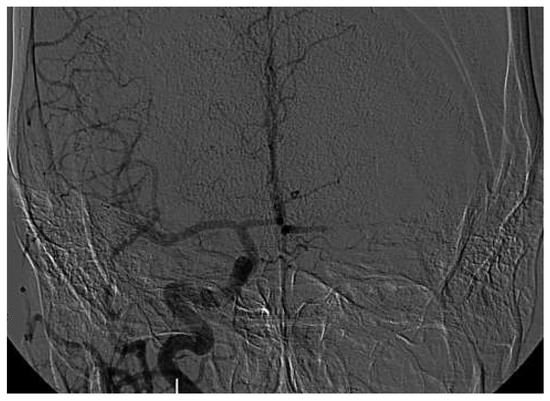

3 pages, 1632 KB

Case Report

Mechanical Thrombectomy After Embolic Internal Carotid Artery Occlusion in Acute Stroke

by Christophe A. Wyss, Anahita Dastoor and Roberto Corti

Cardiovasc. Med. 2014, 17(2), 51; https://doi.org/10.4414/cvm.2014.00204 - 19 Feb 2014

Viewed by 360

Abstract

A 34-year old woman presented to the emergency department with a wake-up stroke, after onset of a sensomotoric paresis of the right arm and motoric aphasia [...] Full article

Show Figures

Figure 1